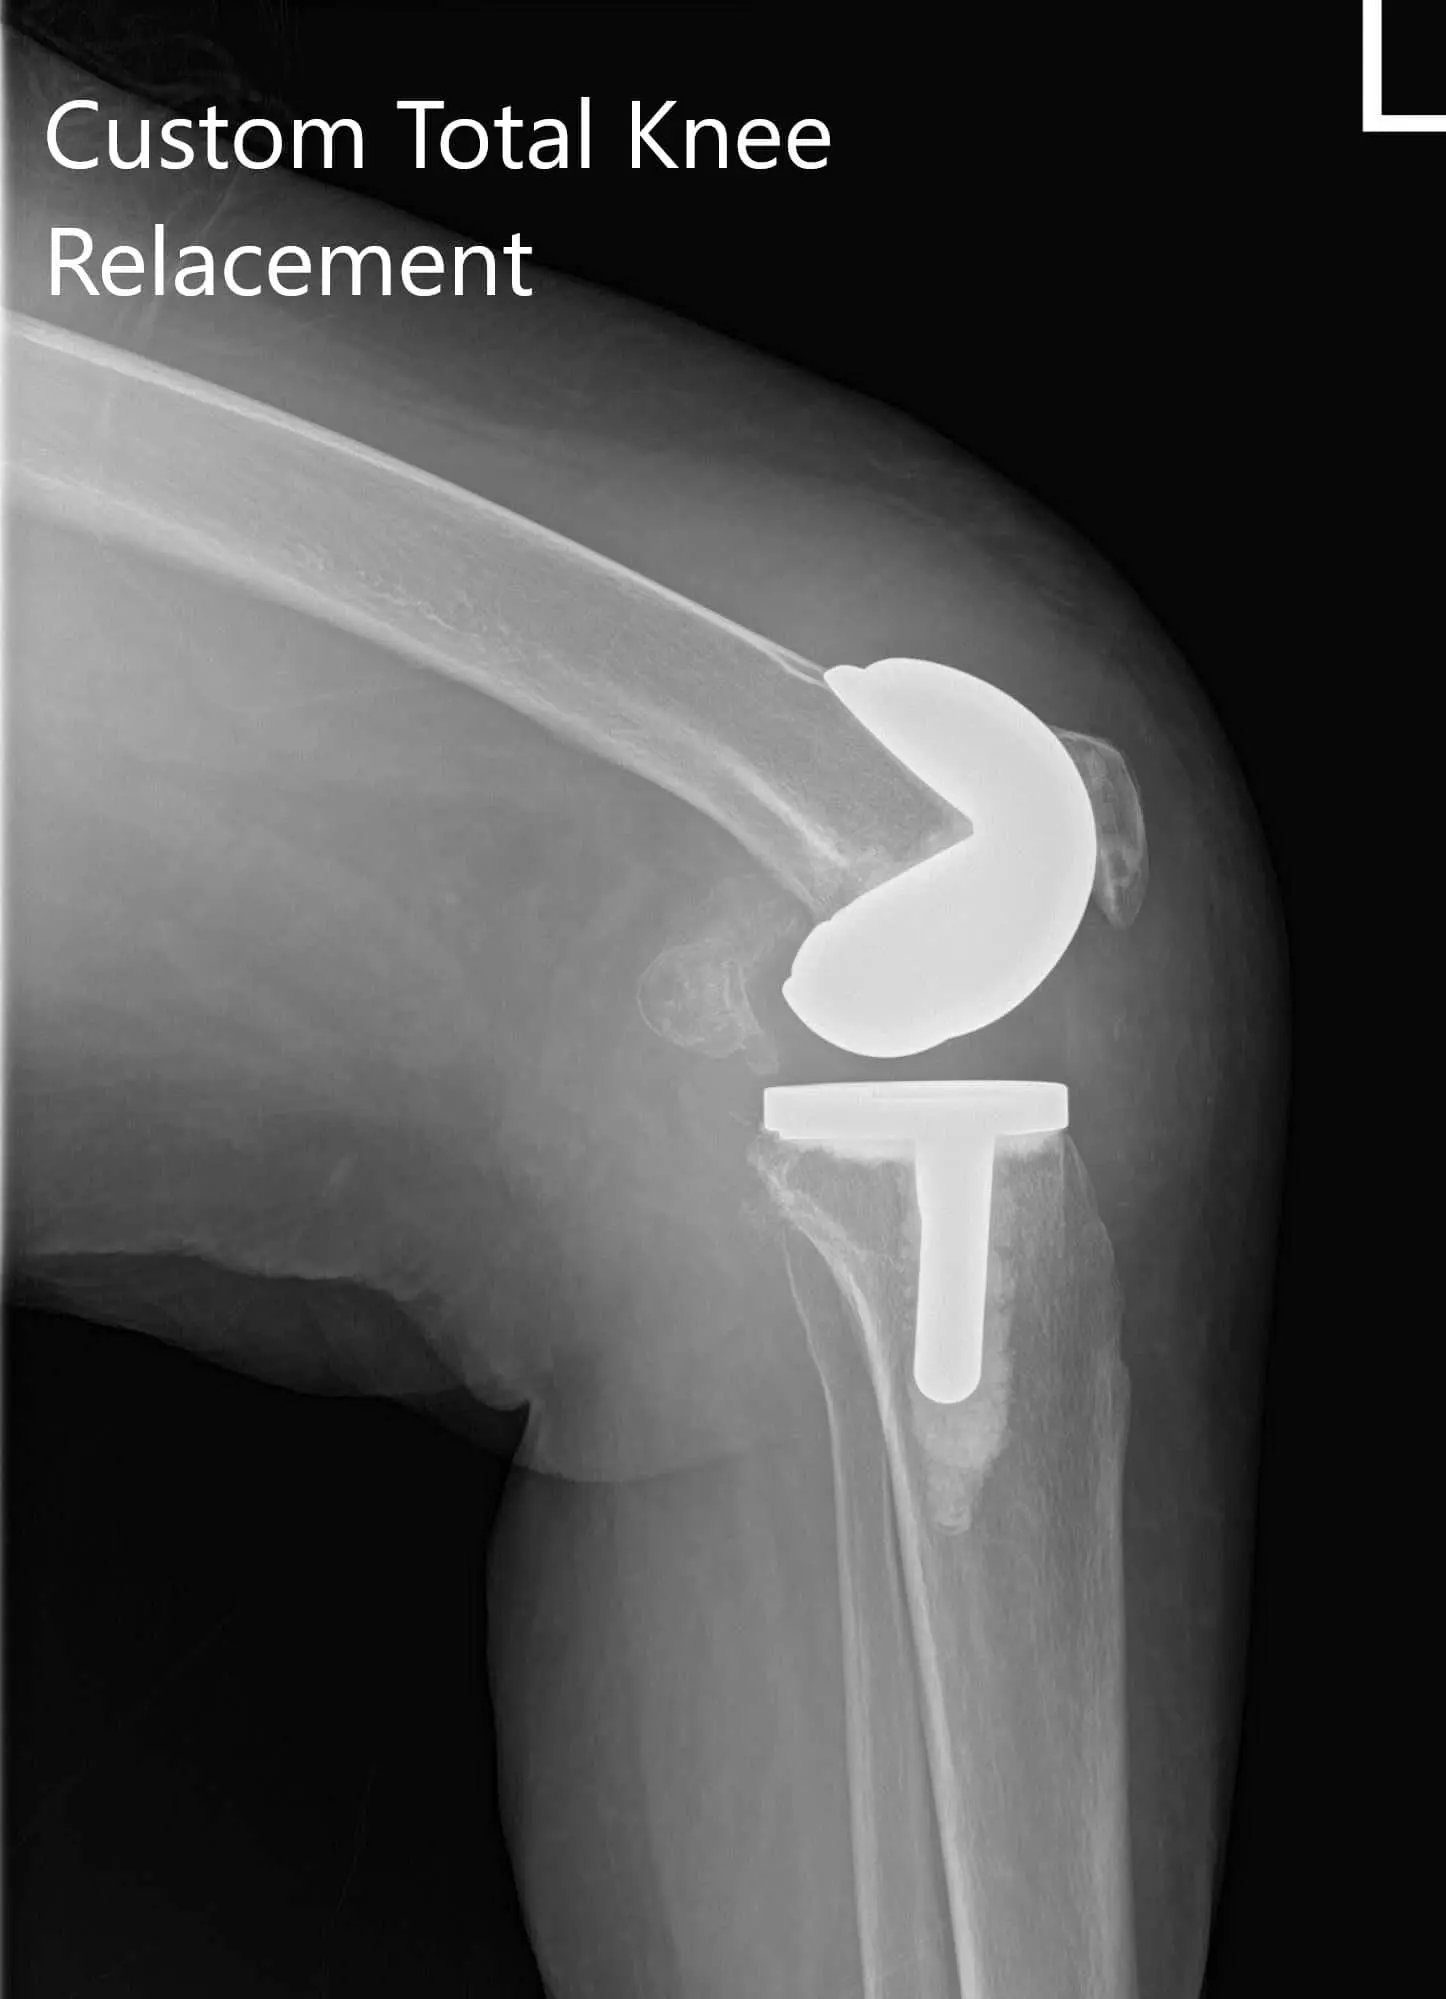

Postoperative X-ray showing AP and lateral views of the right and the left knee joint